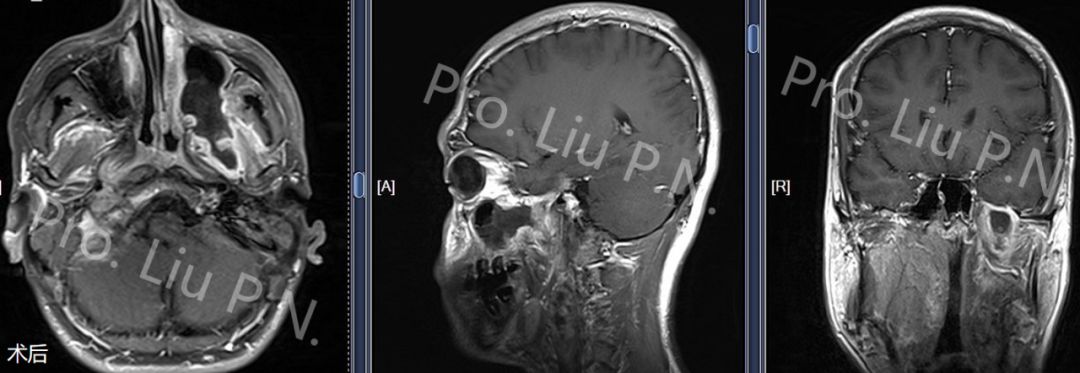

十二、经上颌窦-蝶骨大翼-海绵窦入路手术案例

--下颌神经起源神经鞘瘤

![]()